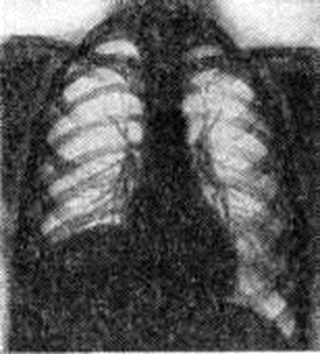

Паралич верхнего ствола плечевого сплетения у взрослых также сопровождается медленным и неуклонным развитием остеопороза и атрофией костей повреждённой конечности. Первые признаки остео- пороза, а затем и атрофии обычно развиваются спустя 3—4 месяцев после повреждения. При повреждении плечевого сплетения как у ребёнка, так и у взрослого может повреждаться и диафрагмальный нерв, в результате чего наступает парез соответствующего купола диафрагмы. В этих случаях при рентгенологическое исследовании определяется высокое стояние паретически расслабленного купола диафрагмы (рисунок 3) и парадоксальные дыхательные движения.

Рис. 3.

Рентгенограмма грудной клетки больного при параличе диафрагмального нерва справа: высокое стояние паретически расслабленного купола диафрагмы.